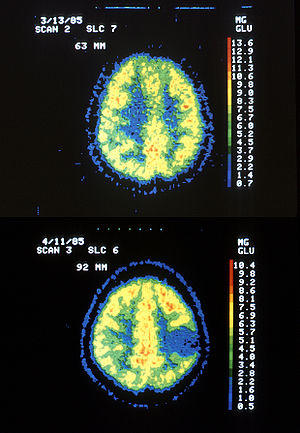

Two PET images — the upper of which shows a normal brain and the lower shows astrocytoma.